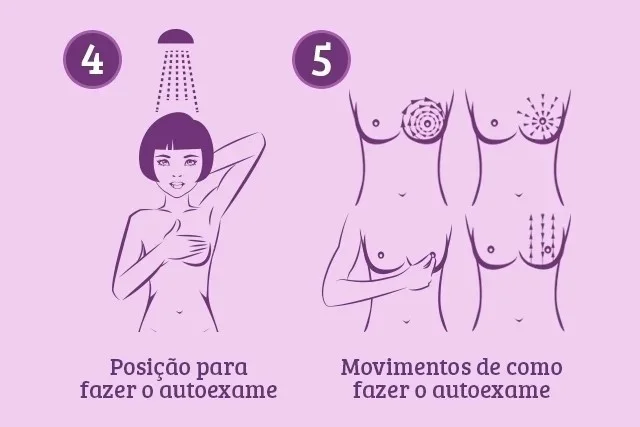

O famoso autoexame é extremamente importante na identificação precoce da doença. No entanto, para fazê-lo corretamente é importante realizar a avaliação em três momentos diferentes: em frente ao espelho, em pé e deitada

Faça o autoexame. Em frente ao espelho, tire toda a roupa e observe os seios com os braços caídos. Em seguida, levante os braços e verifique as mamas. Por fim, coloque as mãos apoiadas na bacia, fazendo pressão para observar se existe alguma alteração na superfície dos seios

A palpação de pé deve ser feita durante o banho com o corpo molhado e as mãos ensaboadas. Para isso, levante o braço esquerdo, colocando a mão atrás da cabeça. Em seguida, apalpe cuidadosamente a mama esquerda com a mão direita. Repita os passos no seio direito

A palpação deve ser feita com os dedos da mão juntos e esticados, em movimentos circulares em toda a mama e de cima para baixo. Depois da palpação, deve-se também pressionar os mamilos suavemente para observar se existe a saída de qualquer líquido

Por fim, deitada, coloque a mão esquerda na nuca. Em seguida, com a mão direita, apalpe o seio esquerdo verificando toda a região. Esses passos devem ser repetidos no seio direito para terminar a avaliação das duas mamas